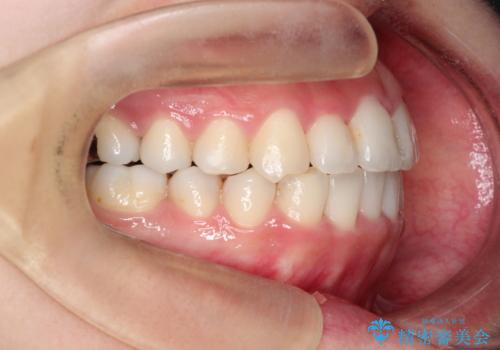

【ワイヤー矯正】前歯の凸凹を非抜歯で治療

- 前歯の凸凹を主訴に来院されました。

側方拡大にてスペースを作ることにより綺麗に前歯を並べることができました。

前歯の凸凹がある場合は治療計画を立てる上でスペースをどのように作るかが重要になります。

今回の場合は主に側方拡大でスペースの確保を行いました。